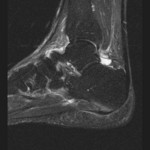

[画像診断]足底腱膜炎 2010-07-16